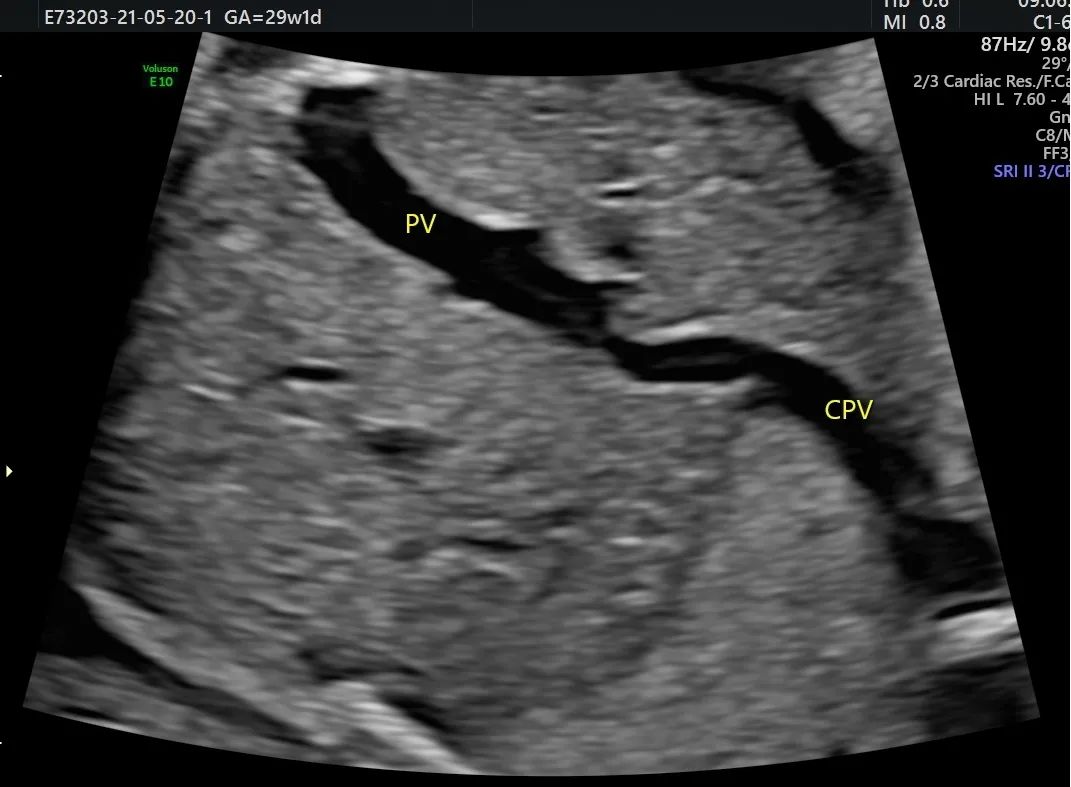

完全性肺静脉异位引流

XXX 女 48 岁 G1PO 孕 29W1D 既往无不良孕史

外院系统、四维超声未发现心脏显著异常,心脏超声检查时发现左心系统小,瓣环及主动脉峡部略细,肺静脉异位引流待排。为进一步明确诊断,特来我院请张军教授会诊。我科行胎心检查时发现左房内未见肺静脉开口;四只肺静脉在左房后方形成共同静脉干后向下走形进入肝静脉。遂做出完全性肺静脉异位引流(心下型)的诊断,为了解生后手术情况,患者到上级医院会诊,证实了此诊断。

正常情况下,四支肺静脉均应引流入左心房。完全性肺静脉异位引流指四条肺静脉形成共同肺静脉干,未引流入左心房,而通过不同途径引流入右心房,右心房内的动静脉混合血一部分经三尖瓣入右心室、肺动脉,一部分经房间隔缺损引流入左心房供应体循环。

TAPVC 发病率低、畸形复杂,诊断相对困难。因存在大量右向左分流,所以新生儿期即出现紫绀、呼吸困难等缺氧症状,情况危急,需早期手术。如果在产前能做出明确诊断,有利于生后做好相应处理措施。